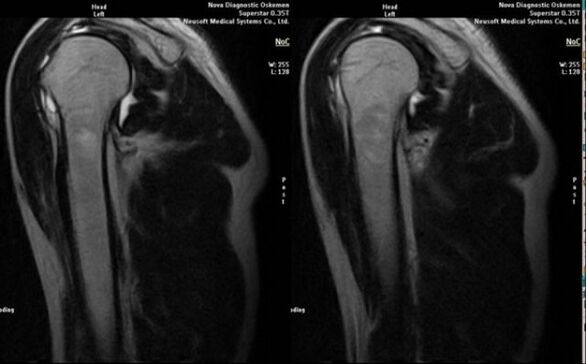

O principal método diagnóstico para detectar a osteoartrite deformante da articulação do ombro é a radiografia simples.

- ressonância magnética e tomografia computadorizada;

Os sinais que indicam diretamente o desenvolvimento de artrose incluem o aparecimento de estreitamento significativo do espaço articular, esclerose das estruturas subcartilaginosas, adelgaçamento da própria camada de condrócitos, aparecimento de osteófitos e deposição de cristais de sal no fluido intra-articular.